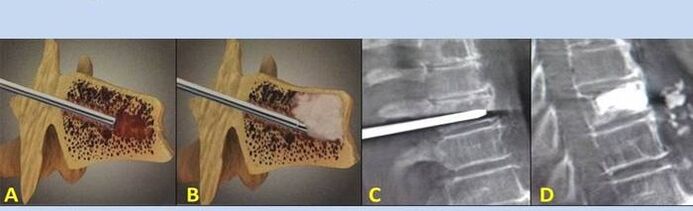

- Nucléoplastie – ablation du noyau du disque intervertébral. L'opération soulage la pression sur les terminaisons nerveuses.

- Vertébroplastie par ponction – méthode de stabilisation des vertèbres. Au cours de l’intervention, le médecin remplit les cavités vertébrales avec du ciment osseux.